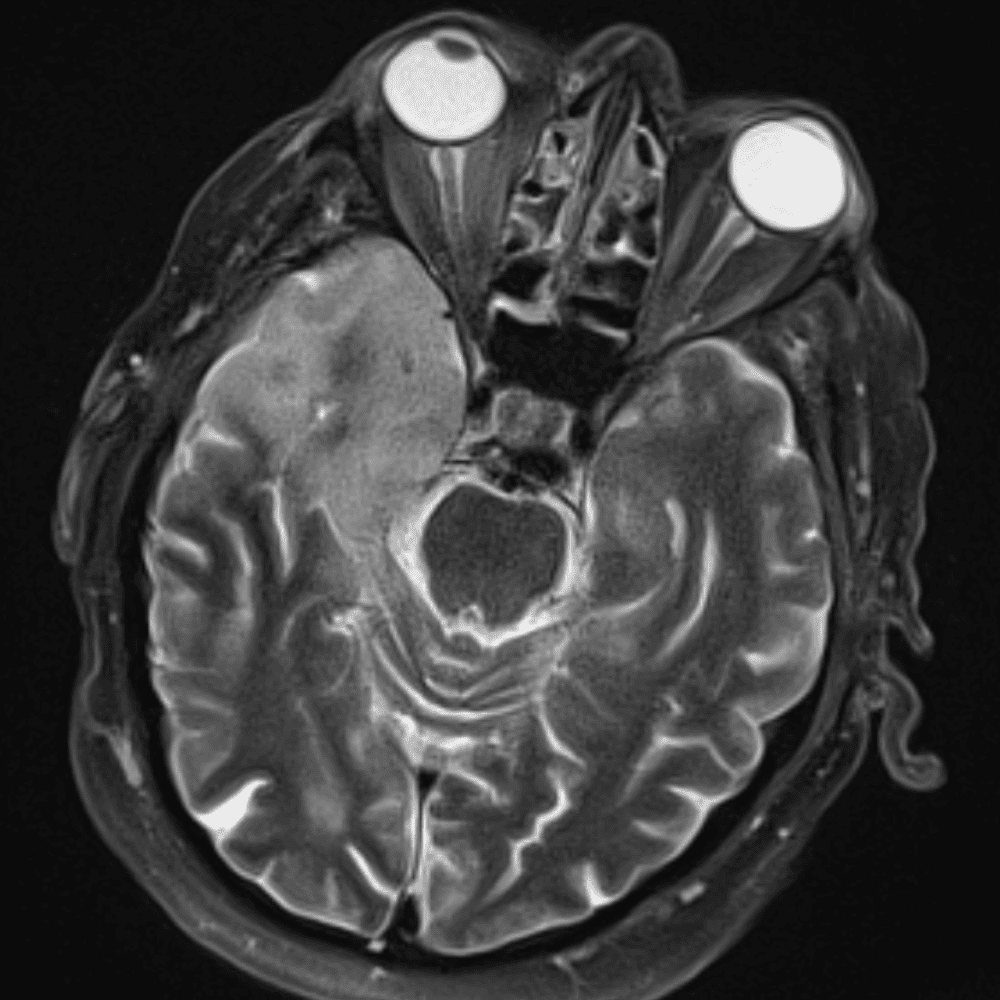

๋‹น์ง ์‹œ ํ”ํžˆ ๋ณผ ์ˆ˜ ์žˆ๋Š” ์‚ฌ๋ก€์˜ ์ „ํ˜•์ ์ธ ์˜ˆ๋ฅผ ํฌํ•จํ•ฉ๋‹ˆ๋‹ค.

39 ์‚ฌ๋ก€

์—ฐ์Šต

๋ฏธ๋ฌ˜ํ•˜๊ฑฐ๋‚˜ ์–ด๋ ค์šด ์‚ฌ๋ก€์™€ ์ผ๋ถ€ ์ •์ƒ ์‚ฌ๋ก€๋ฅผ ํฌํ•จํ•˜์—ฌ ๋‹น์ง์„ ์‹œ๋ฎฌ๋ ˆ์ด์…˜ํ•ฉ๋‹ˆ๋‹ค.

50 ์‚ฌ๋ก€